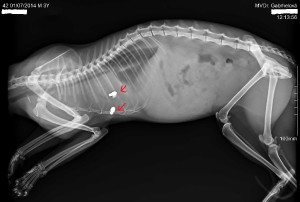

Střelná poranění u koček

Na zde vložených fotografiích je prezentováno několik rentgenových snímků letošních pacientů,u kterých bylo náhodně diagnostikováno střelné poranění,třeba i několik let staré.Co to asi naznačuje o našem celospolečenském vztahu ke zvířatům posuďte sami.